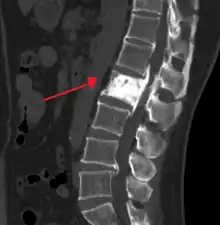

![]() | |

| "This 92 year-old male patient presented for assessment of sudden inability to move half his body. An incidental finding was marked thickening of the calvarium. The diploic space is widened and there are ill-defined sclerotic and lucent areas throughout. The cortex is thickened and irregular. The findings probably correspond to the 'cotton wool spots' seen on plain films in the later stages of Paget’s disease." | |